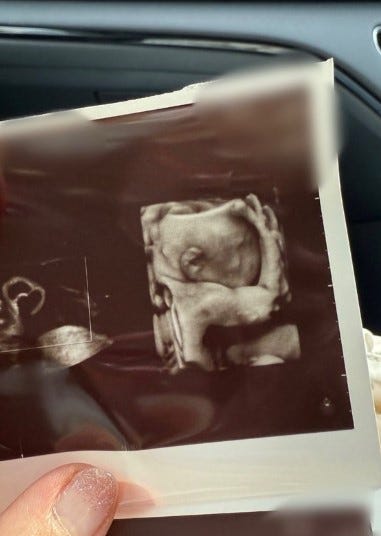

タレントの辻希美が12日、自身の公式SNSを更新。夫の杉浦太陽と妊婦検診に行った様子を報告し、第5子のエコー写真を公開した。

辻は「検診日でした 4Dに映ったベビちゃん…顔を手で隠していて顔は見えなかったんだけど腕…ムキムキじゃない?」というコメントとともに、エコー写真を公開。「え?!本当に?!ってなりました たぁだ…元気にすくすく育ってくれていて何よりです」と順調な成長への安堵感を記した。また、検診後に杉浦と「つるとんたん」に行ったことを食事風景写真とともに報告。「検診日デート 産まれたらこういう時間もとれなくなるから今のうちに2人時間満喫したい」と夫婦の時間を大切にする気持ちを綴っている。